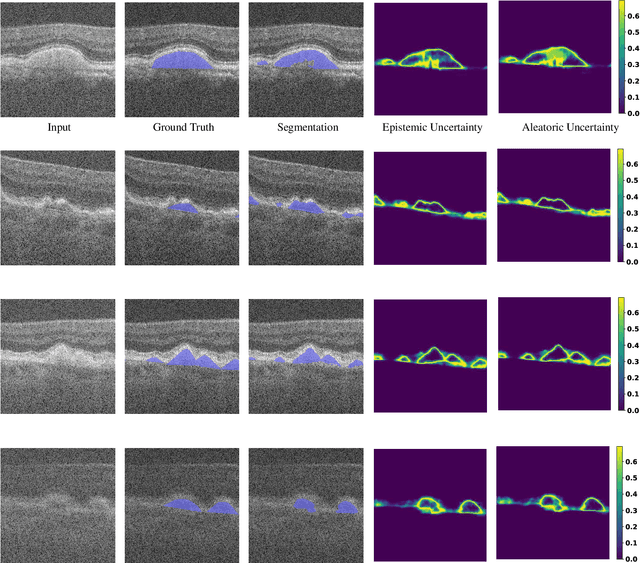

Abstract:Optical coherence tomography (OCT) is commonly used to analyze retinal layers for assessment of ocular diseases. In this paper, we propose a method for retinal layer segmentation and quantification of uncertainty based on Bayesian deep learning. Our method not only performs end-to-end segmentation of retinal layers, but also gives the pixel wise uncertainty measure of the segmentation output. The generated uncertainty map can be used to identify erroneously segmented image regions which is useful in downstream analysis. We have validated our method on a dataset of 1487 images obtained from 15 subjects (OCT volumes) and compared it against the state-of-the-art segmentation algorithms that does not take uncertainty into account. The proposed uncertainty based segmentation method results in comparable or improved performance, and most importantly is more robust against noise.

Abstract:Age-related macular degeneration (AMD) is one of the leading causes of permanent vision loss in people aged over 60 years. Accurate segmentation of biomarkers such as drusen that points to the early stages of AMD is crucial in preventing further vision impairment. However, segmenting drusen is extremely challenging due to their varied sizes and appearances, low contrast and noise resemblance. Most existing literature, therefore, have focused on size estimation of drusen using classification, leaving the challenge of accurate segmentation less tackled. Additionally, obtaining the pixel-wise annotations is extremely costly and such labels can often be noisy, suffering from inter-observer and intra-observer variability. Quantification of uncertainty associated with segmentation tasks offers principled measures to inspect the segmentation output. Realizing its utility in identifying erroneous segmentation and the potential applications in clinical decision making, here we develop a U-Net based drusen segmentation model and quantify the segmentation uncertainty. We investigate epistemic and aleatoric uncertainty capturing model confidence and data uncertainty respectively. We present segmentation results and show how uncertainty can help formulate robust evaluation strategies. We visually inspect the pixel-wise uncertainty and segmentation results on test images. We finally analyze the correlation between segmentation uncertainty and accuracy. Our results demonstrate the utility of leveraging uncertainties in developing and explaining segmentation models for medical image analysis.